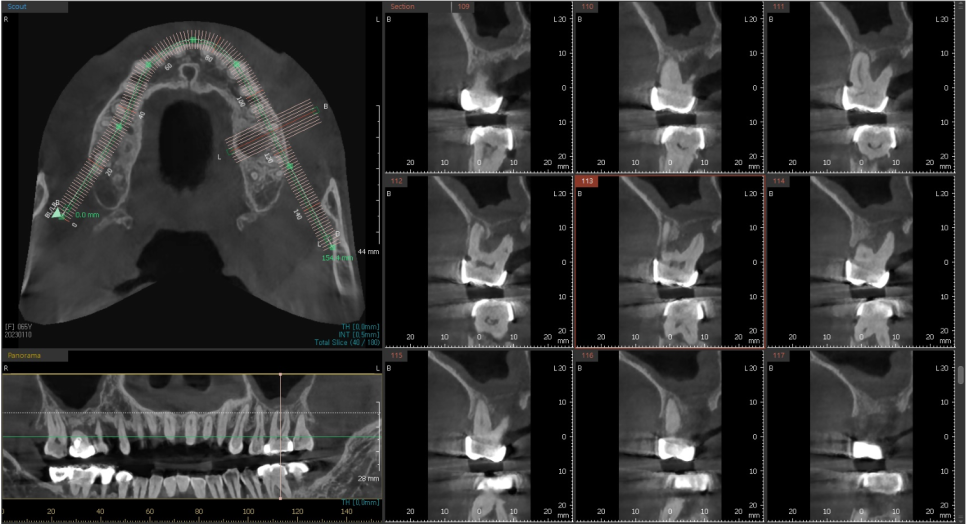

수술하기전에 삼차원 CT와 삼차원 구강 스캔 데이터를 가지고,

먼저 식립 위치를 시뮬레이션 해본 후

정확히 식립할 수 있는 네비게이션 장치를 제작합니다.

이를 맞춤장치를 제작한다고해서 "네비게이션 임플란트"라고 하는데요.

저희는 해당 디지털 기술을 적극 도입하여 뼈 상태가 좋은 자리에

정확하게 안전하게 시술하고 있습니다.

CT 캡쳐 사진

CT를 분석하여 미리 계획해둔 자리에

가이드를 장착하고 심은 덕분에

해당자리 상악동 손상없이 안전하게

상악동 거상술과 임플란트 식립을 마쳤습니다.

이번에 진행한 상악동 거상술은

상악동 수직 거상술로 수압을 이용해 막을 들어올려서

안쪽에 뼈를 채우고 해당자리에

계획한 굵기와 길이의 픽스처를 심을 수 있게 하는 방법입니다.